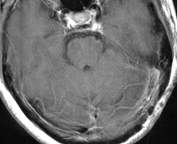

鞍結節部髄膜腫

鞍結節部髄膜腫とは、頭蓋底の奥深い場所にある骨の出っ張りに付着するように存在する髄膜腫です。その近くに視神経が接しているため、腫瘍を放置しておくとわずかに大きくなるだけで視神経を圧迫し始めます。手術で摘出しないと、そのまま失明の危険があります。この部位の髄膜腫はたとえ腫瘍の大きさが小さくても手術を勧めます。

特に視力低下・視野障害の自覚があれば、放置しておくと失明する可能性が高いため、手術を受けた方が良いと考えます。

(術前MRI)

(術後MRI)